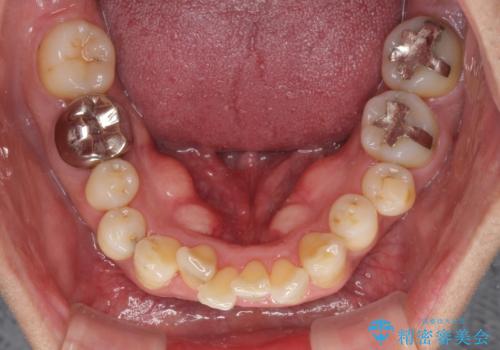

- 八重歯を気にして来院された患者様です。

上顎前歯の突出感と右上の八重歯を気にされていたので、上顎左右の第一小臼歯2本を抜歯し、ワイヤー装置にて矯正治療を行うこととしました。

食いしばりにより奥歯がすり減っており、咬み合わせが定まるまで時間がかかりましたが、整った口もに仕上がりました。